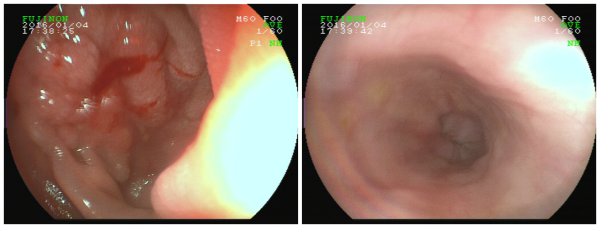

• 小小牙签竟酿大祸瑞康无痛胃镜异物取出术为男子解忧

小小牙签竟酿大祸瑞康无痛胃镜异物取出术为男子解忧

要不是在瑞康医院做了胃镜下异物取出术,林先生还不知道导致自己腹痛一个多星期的罪魁祸首竟然是藏在十二指肠球降交界处约6.5cm长的牙签! ...

发布时间:2016-01-06 来源: